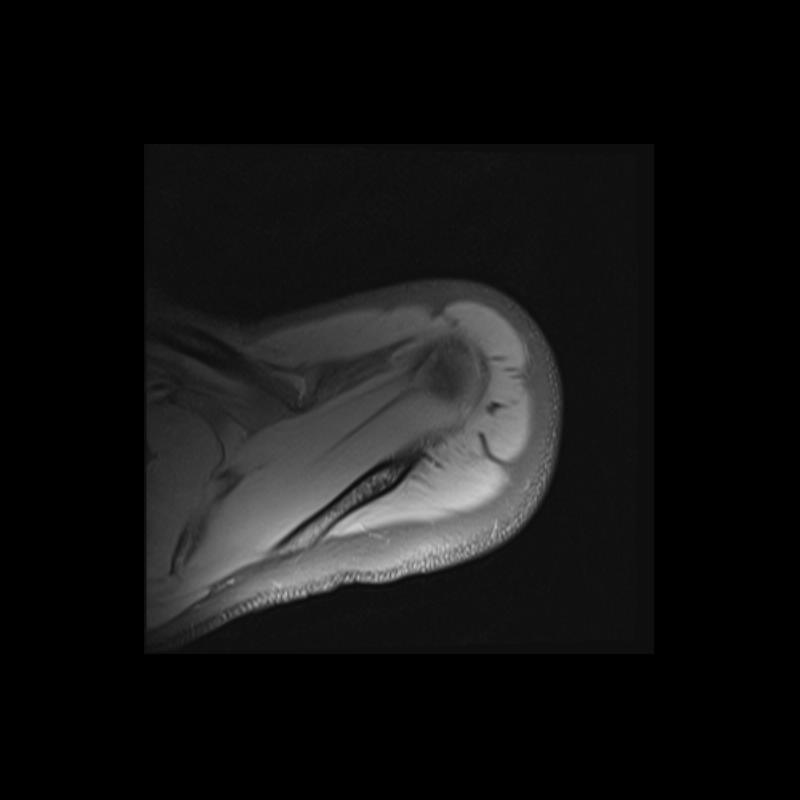

Shoulder MRI Anatomy